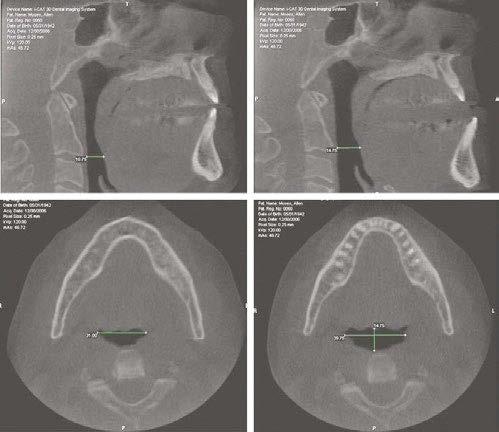

Here’s more good news. In this issue of Dental Sleep Practice, our Cover Story spotlights the latest in dental sleep medi cine solutions to treat OSA patients more effectively. SomnoMed’s second annual SomSummit focused on vetting the value of all sleep therapies and explored the fun damental research that supports them in improving, and even defining, OSA treat ment success. In our CE, “Interarch Jaw Registration Devices for Oral Sleep Appli ances,” Dr. Allen J. Moses explains bilat eral molar stabilization and creating a more open airway. In “Tongue Tie is Not Your Only

the patient that revealed symptoms of severe sleep bruxism, excessive daytime sleepiness, and snoring. The patient also complained of having chronic pain in the jaw and masseters, especially when waking up in the mornings. He reported gaining over 10 pounds in the last few years and the presence of hyperten sion which was not responsive to his daily medication.

The patient was referred to complete an in-lab polysomnogram (PSG) since it had been a long time since his previous sleep study.

The results of the PSG indicated the pres ence of severe OSA with an apnea/hypopnea index (AHI) of 43.1/Hr and respiratory dis turbance index (RDI) of 44.8/Hr. The PSG also indicated a REM dom inant OSA with an AHI of 58.6/Hr. The minimum SaO2 was 89.0% with a mean SaO2 of 98.8%. The sleep efficiency was cal culated at 93.4%.

Despite his severe OSA, the patient refused treatment with CPAP and was referred back to Dr. Yousefian’s office to be treated for his OSA and masticatory/temporoman dibular joint disorders (M/ TMJD). His treatment was initiated with bedtime use of the ApnoDent®, an FDA-approved oral appliance (Figure 2) designed to manage his bruxism, M/TMJD issues, snoring, and OSA.

An efficacy test was performed after four weeks of ApnoDent® use; the sleep test results indicated a reduction of AHI to 1.9/Hr with SpO2 nadir of 91%. The Mean SaO2 was 94.7%, and the sleep efficiency was 93.4%

The patient started his 2-year supervision phase and continued to use the ApnoDent

with a lower clear retainer at bedtime.